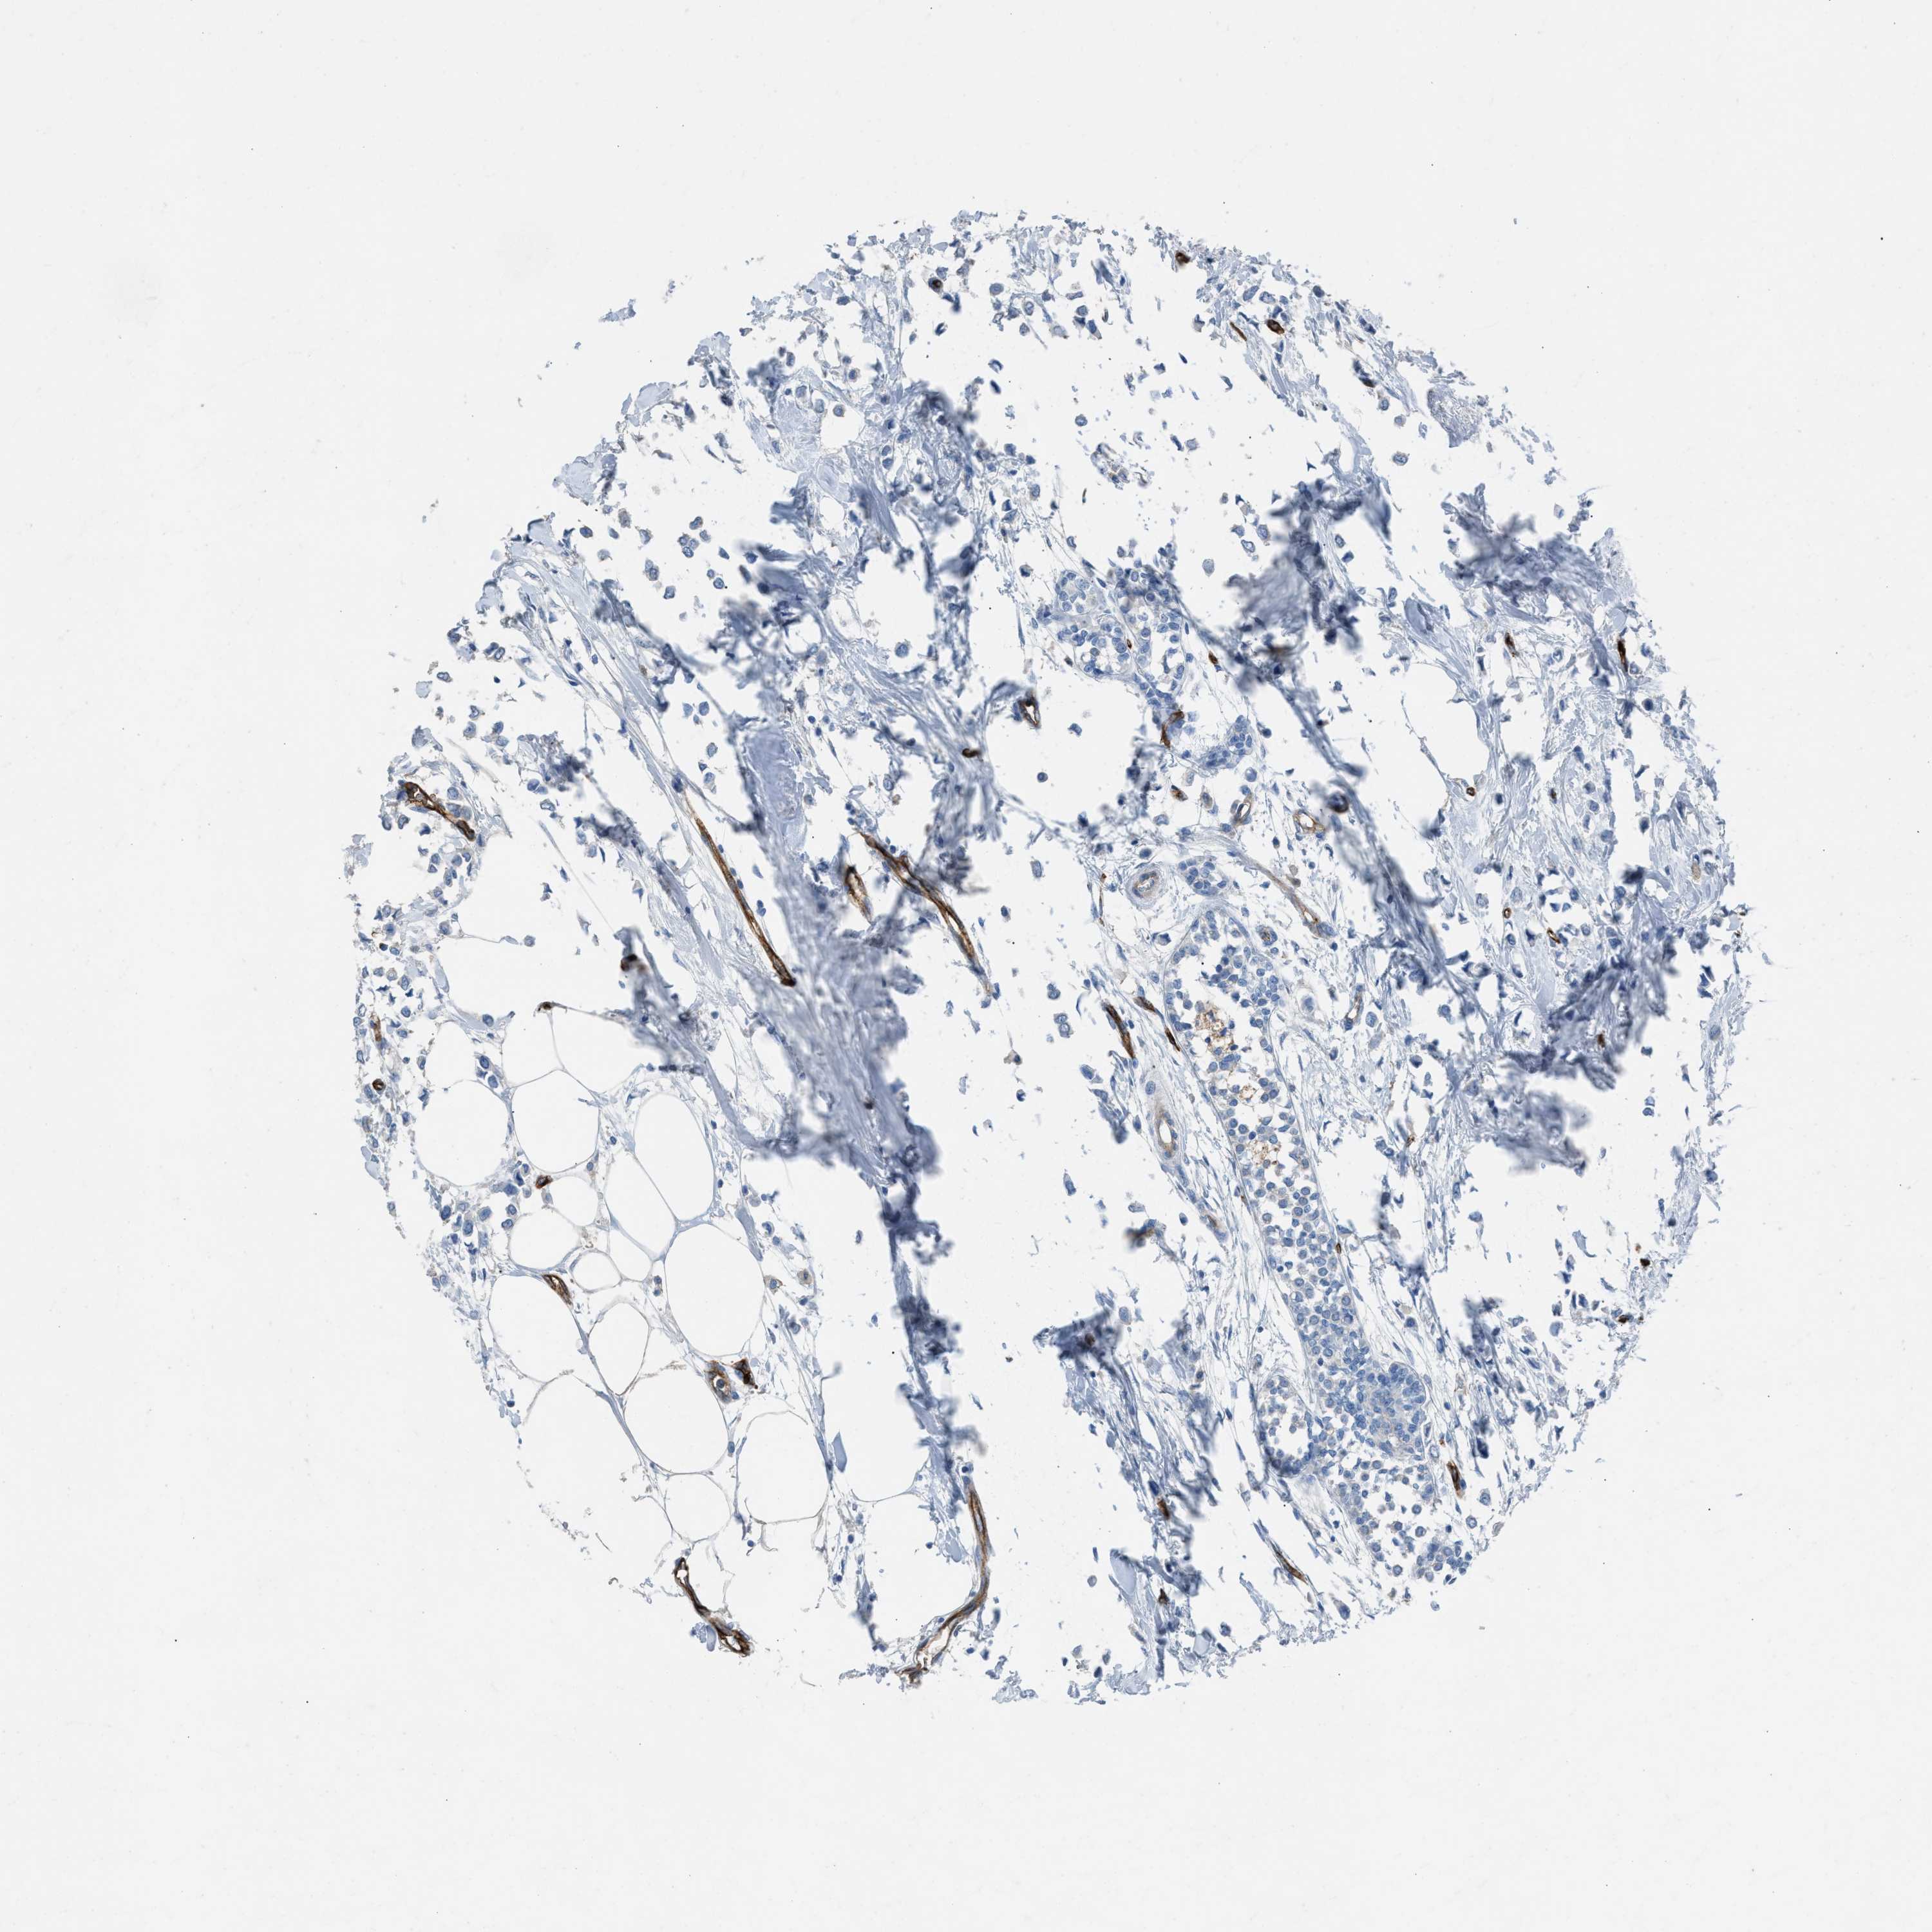

BRCA TCGA BRCA VALIDATION PROTEIN EXPRESSION